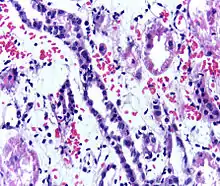

Acute rejection is another possible complication of kidney transplantation; it is graded according to the Banff Classification which incorporates various serologic, molecular and histologic markers to determine the severity of the rejection. Acute rejection can be classified as T-cell mediated, antibody mediated or both (mixed rejection). Common causes of acute rejection include inadequate immunosuppression treatment or non-compliance with the immunosuppressive regiment.[73] Clinical acute rejection (seen in approximately 10-15% of kidney transplants within the first year of transplantation) presents as kidney rejection with associated kidney dysfunction.[73] Subclinical rejection (seen in approximately 5-15% of kidney transplants within the first year of transplantation) presents as rejection incidentally seen on biopsy but with normal kidney function.[73] Acute rejection with onset 3 months or later after transplantation is associated with a worse prognosis.[73] Acute rejection with onset less than 1 year after transplantation is usually T cell mediated, whereas onset greater than 1 year after transplantation is associated with a mixed T cell and antibody mediated inflammation.[73]